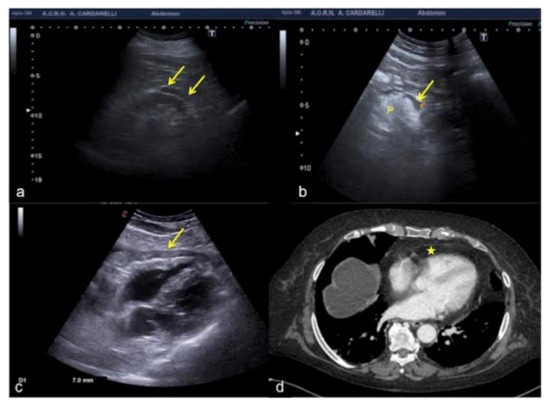

Figure 21. (a) Hypoechoic peri-renal fat, (b) peri-pancreatic fat and (c) pericardial fat misinterpreted as fluid collections (arrows). (d) On CT scan pericardial fat was clearly visible without any fluid collection (star) unlike what was wrongly diagnosed on US scan (c). P: pancreas.